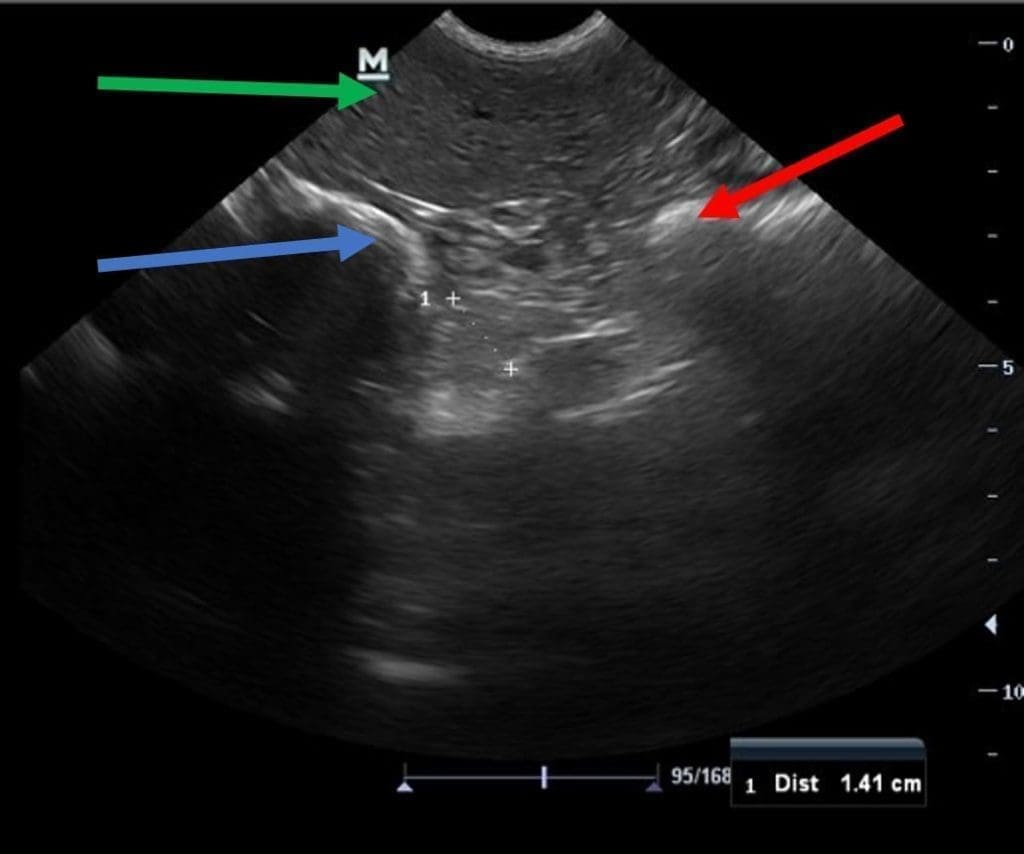

Ultrasonography of the Adrenals >>